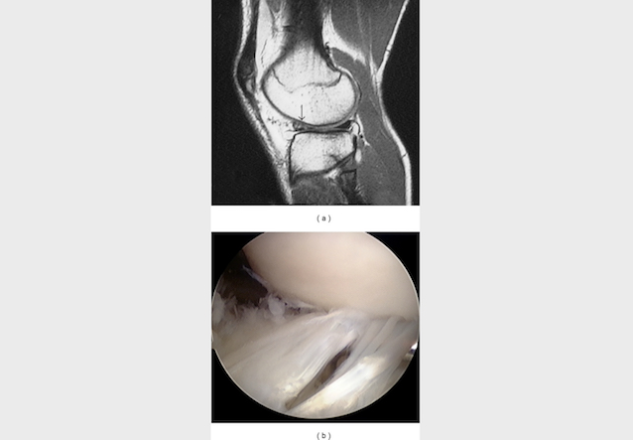

Image from OpenI – Licensed by CC